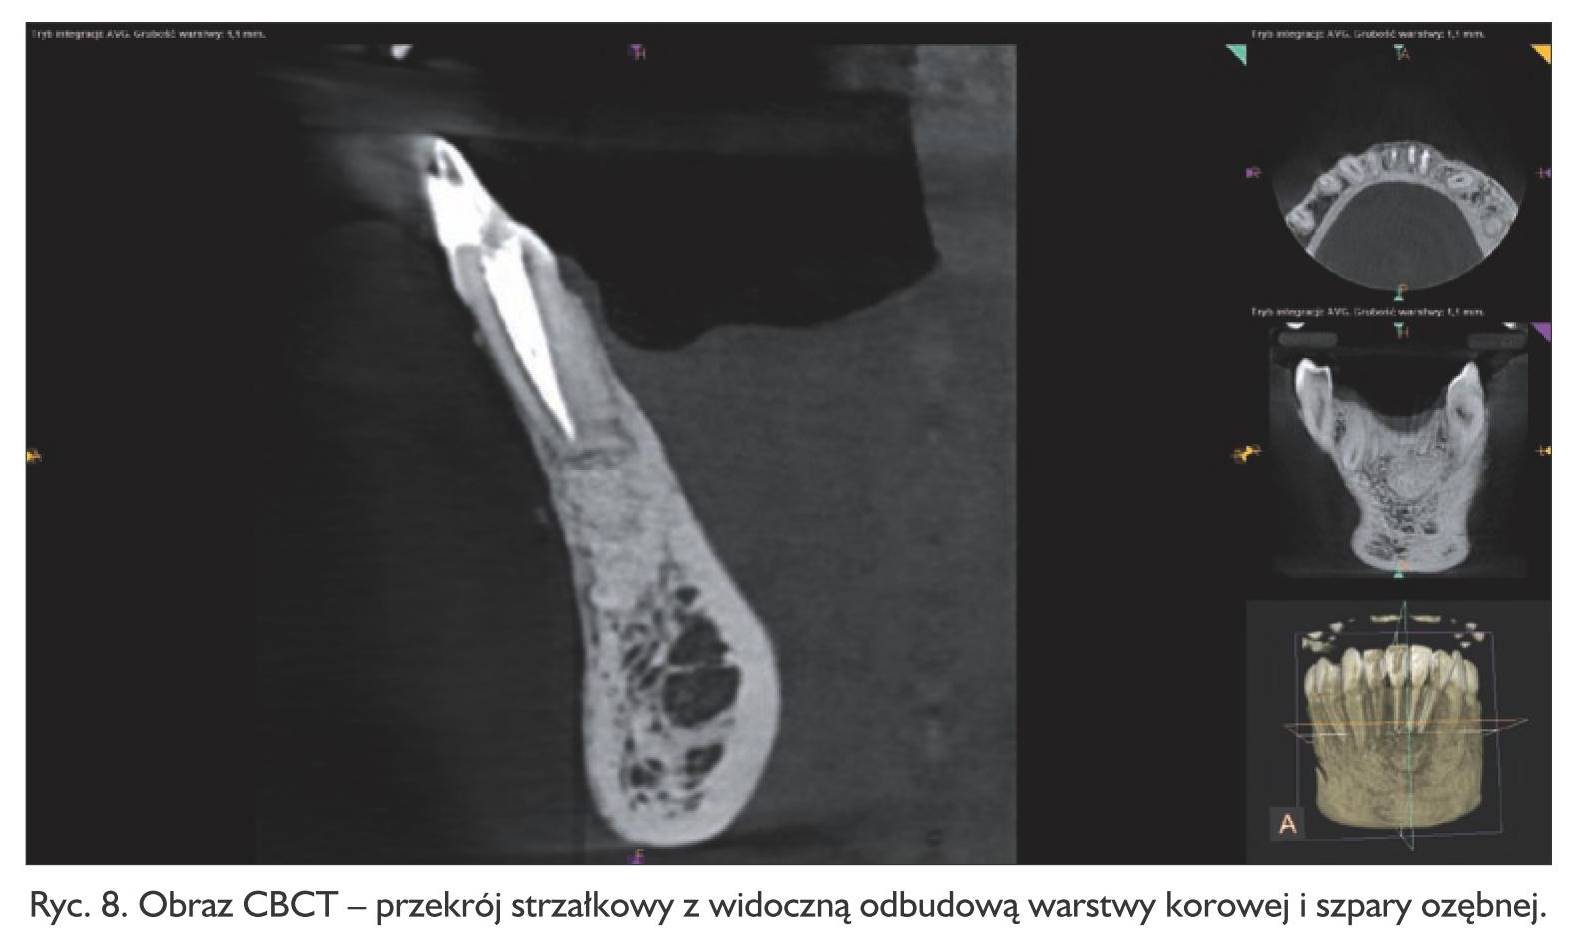

Pacjent zgłosił się po tygodniu w celu usunięcia szwów. Rana goiła się prawidłowo. W opisie badania histologicznego wysłanego materiału potwierdzono wstępną diagnozę cystis odontogenes. Kontrolne badanie tomograficzne wykonano po  6 miesiącach, wykazało ono pełną odbudowę kostną ubytku (ryc. 6, 7, 8, 9). Pacjent od czasu zabiegu nie odczuwał żadnych dolegliwości w tej okolicy.